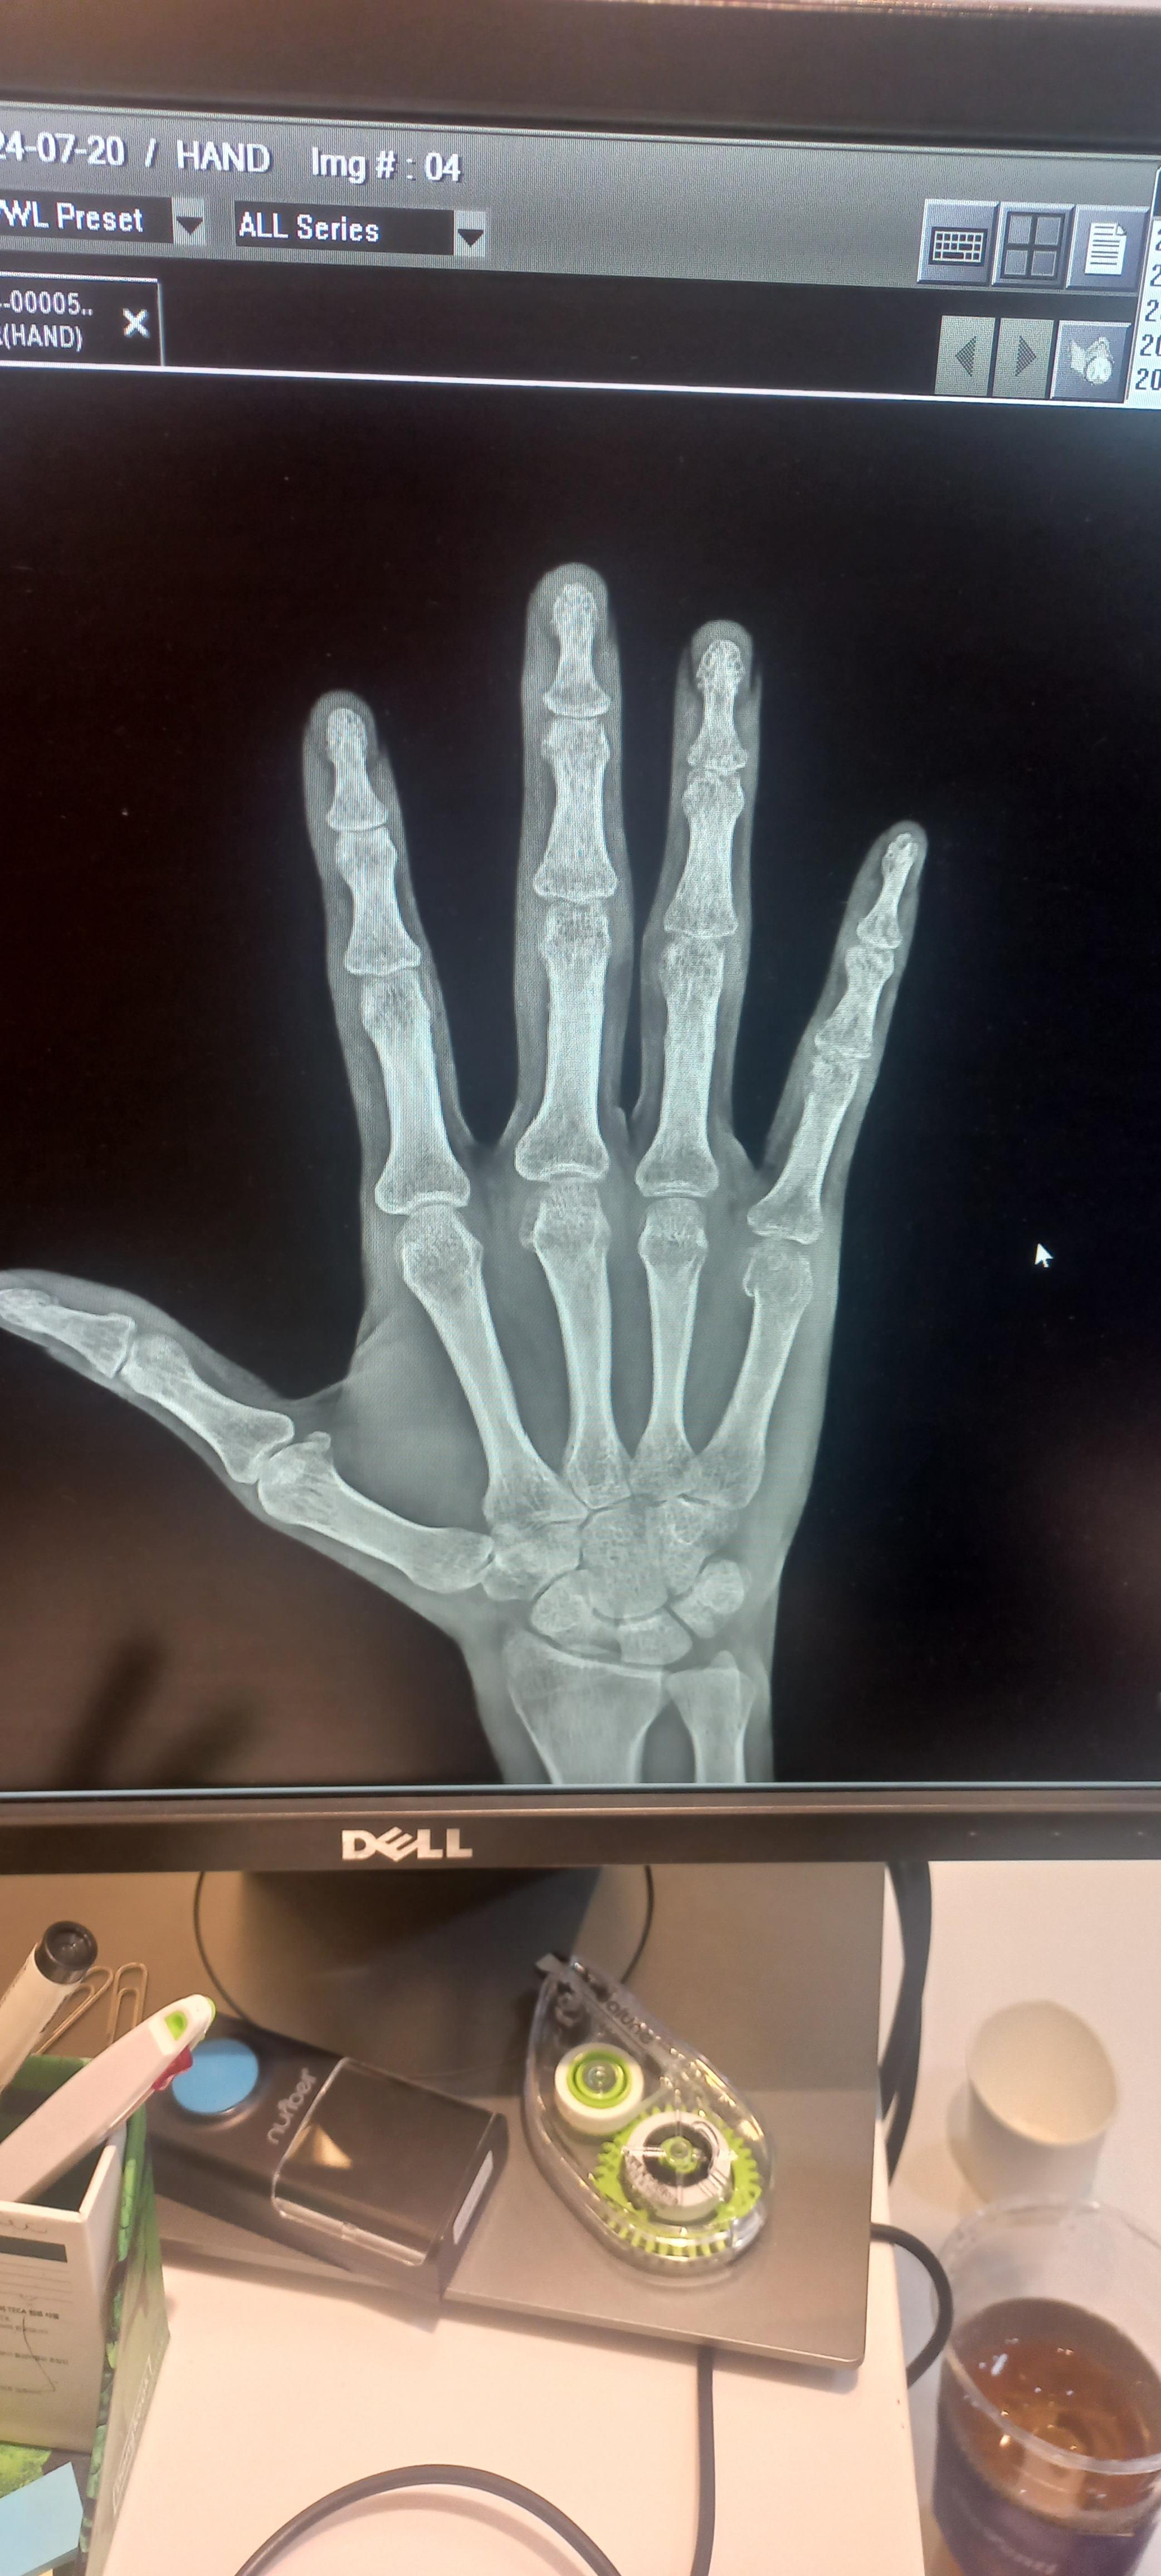

중수골 골절 재활 수술 얼마전에 중수골 골절을 당했어요. 화가 나서 주먹을 벽을 쳤죠. 그러니 부러졌죠. 새끼 손가락 뼈가 중수골이에요. 그래서 병원 치료를 했어요. 6주정도 기브스를 하는데요. 다른 병원은 수술을 요구 하기도 해요. 하지만 기브스로도 되더라구요. 수술은 핀을 박아요. 무섭죠. 그러니 병원 진료는 몇군데 가보세요. 그런후 결정하세요. 뼈는 시간이 지나면붙어요. 하지만 그 이후가 중요한데요. 기브스를 하면 뼈가 굳어요. 손가락이 굳어 버리죠. 저는 깜짝 놀랐어요. 손을 못쓰는 것이 아닌가 하구요. 그래서 열심히 재활을 했답니다. 주먹을 쥐었다. 피세요. 그것을 반복하죠. 이것을 꾸준히 하면 펴져요. 관절은 계속 운동하면 펴져요. 그러니 걱정마세요. 그리고 따뜻한 물에서 운동해도 좋아요..